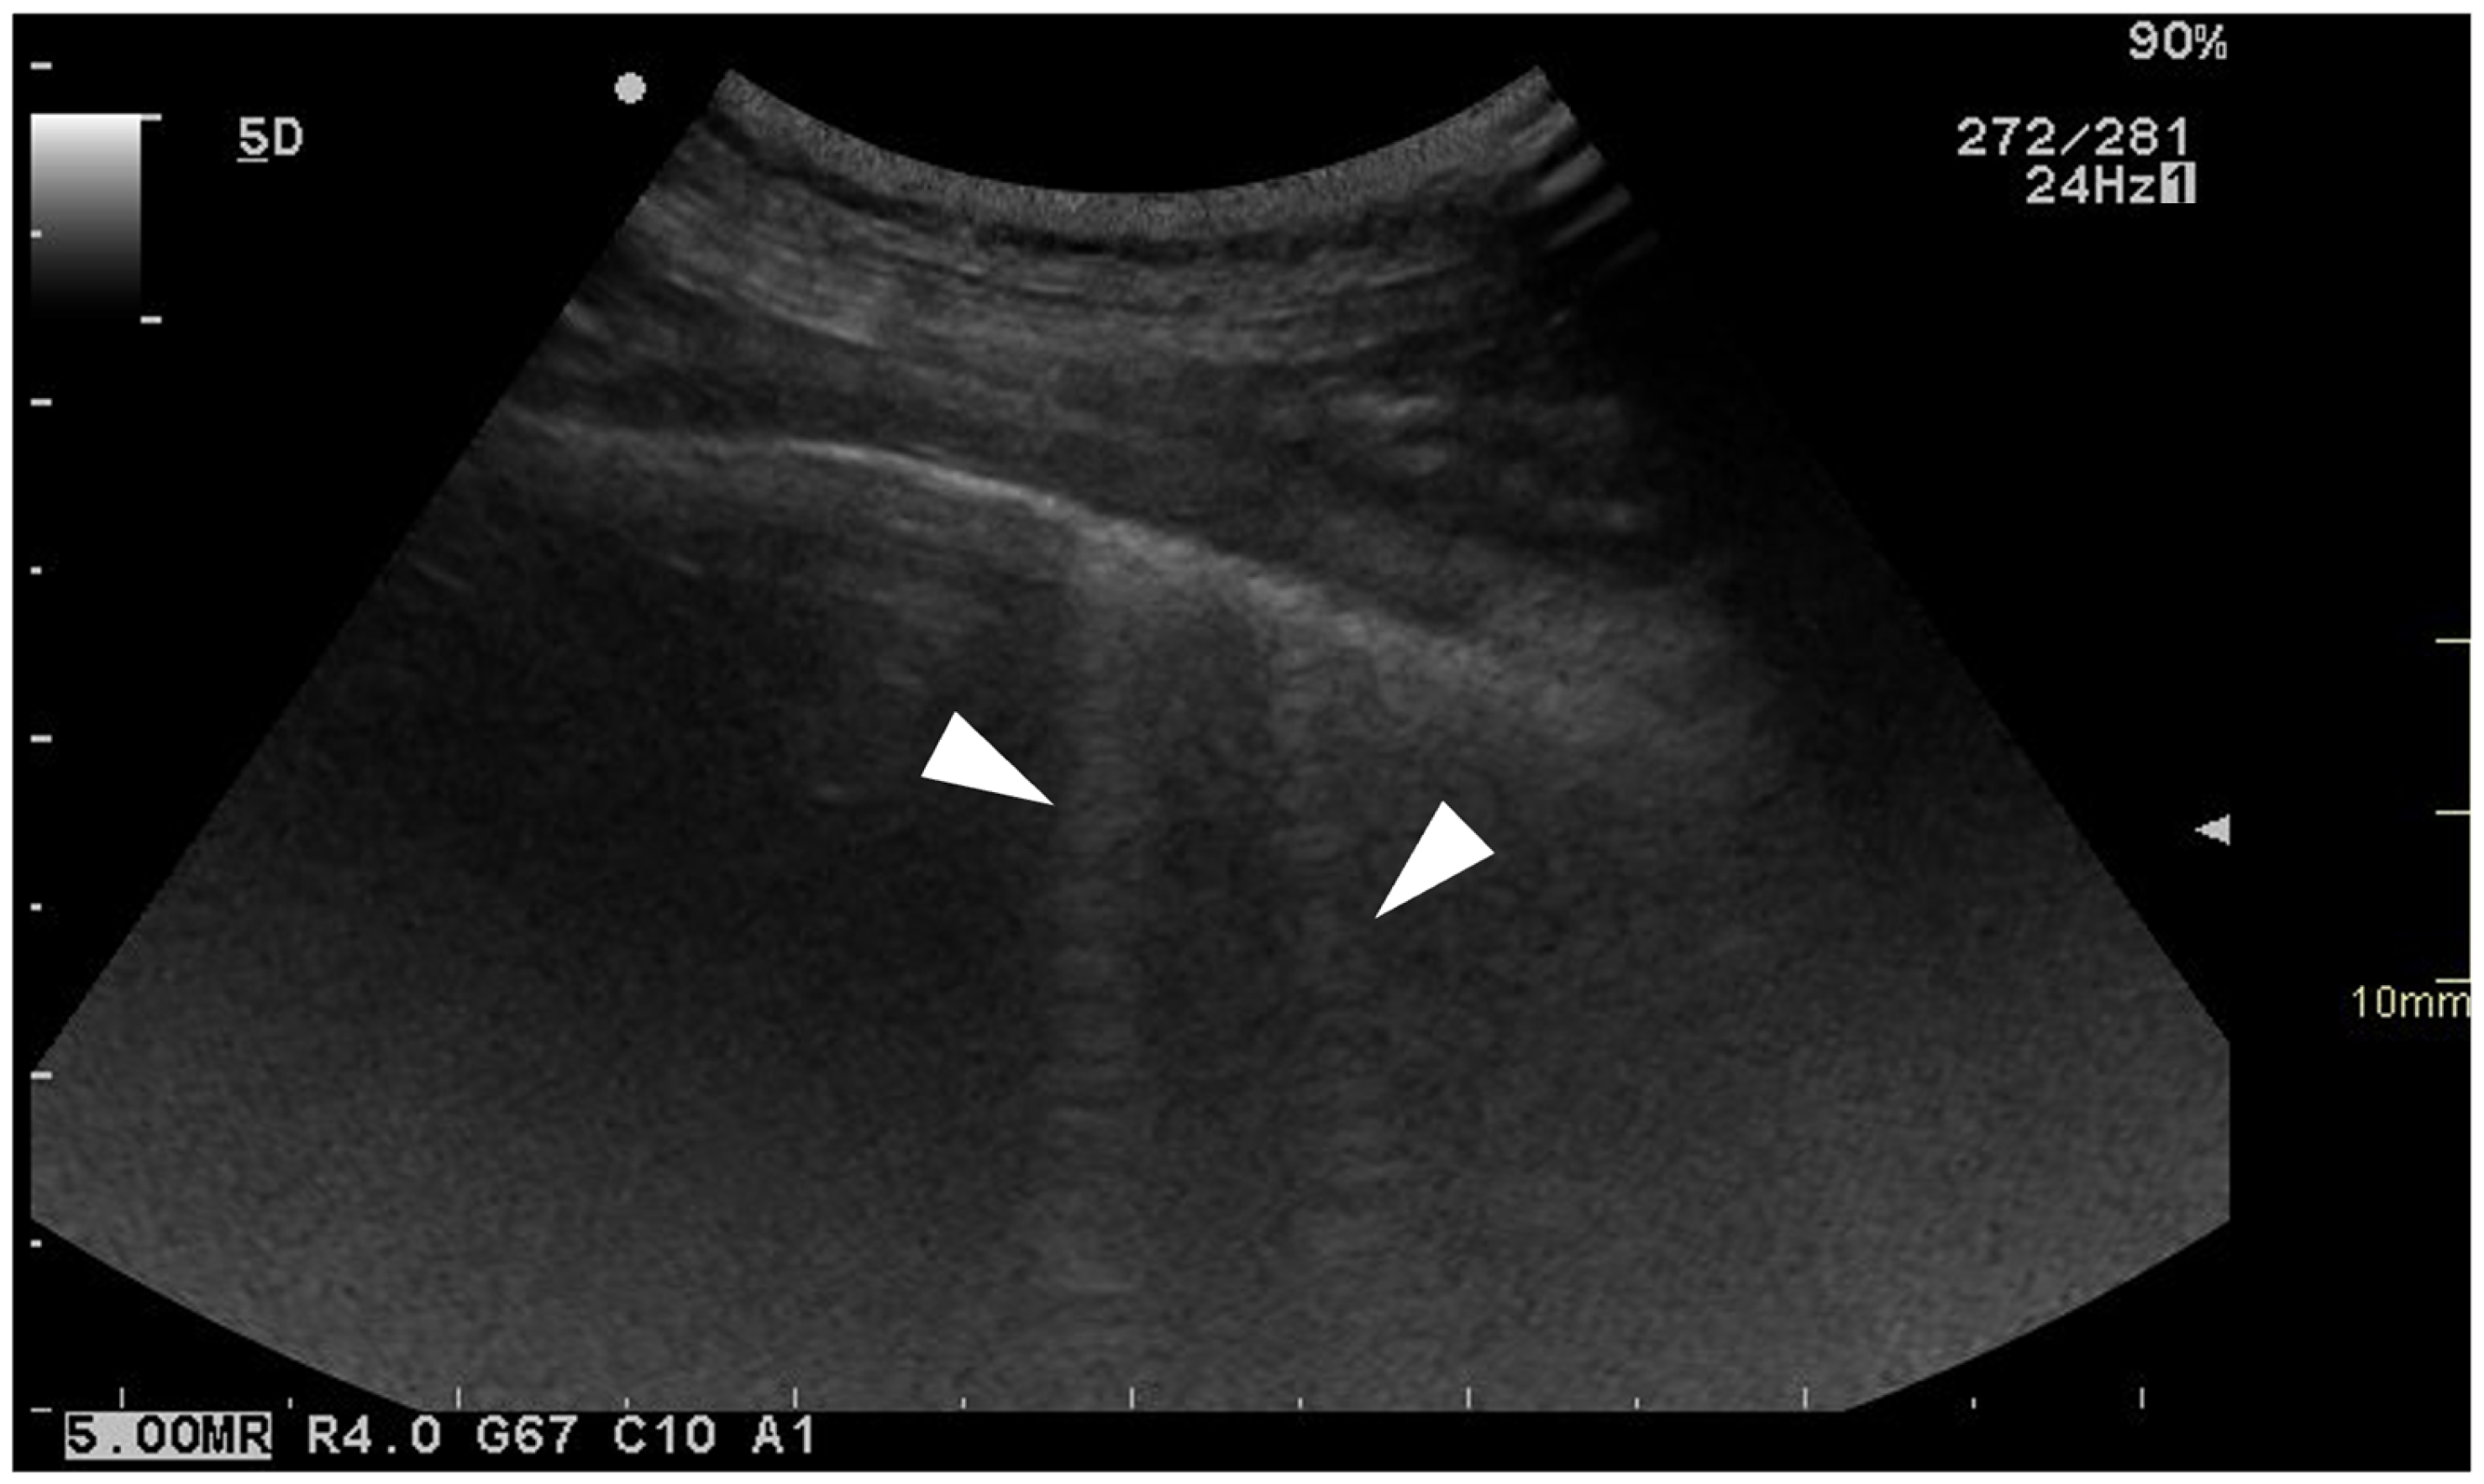

2.1. Thoracic Ultrasonography

3.3.3. Ring-Down Artefacts

3.3.4. Pleural Surface